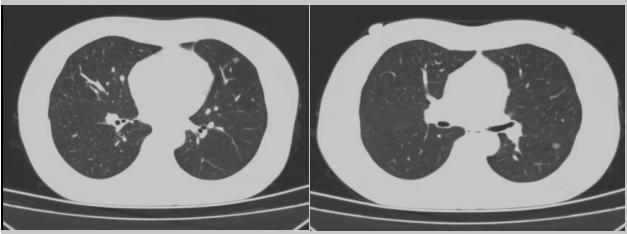

病例一:70多歲的患者王先生于2020年“急性心梗”入院時檢查發(fā)現(xiàn)了肺部結節(jié),王先生沒有在意,其間未規(guī)范復查胸部影像學檢查,于2023年2月份再次發(fā)作心絞痛時,發(fā)現(xiàn)肺結節(jié)已發(fā)展成直徑約2.5cm實性腫塊,患者在家長期口服“替格瑞洛及腸溶阿司匹林”等抗凝藥物,生活可自理,于冠狀動脈二次植入支架后三個月,收住市二院胸外科,經(jīng)心內(nèi)科、麻醉科等多學科會診后,由胸外科主任王松陽、副主任醫(yī)師薛飛及科室團隊行“單孔胸腔鏡下左上肺癌根治術”,術后結合快速康復理念,三天后拔除胸管,一周出院。